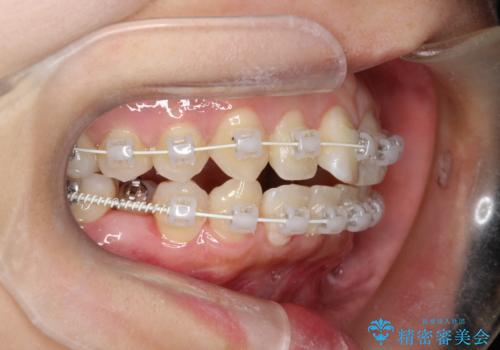

右下第二小臼歯の舌側転移の改善

- 患者様は、右下第二小臼歯が舌側に転移していることが主訴でした。診断の結果、抜歯を伴う矯正治療も検討しましたが、奥歯の遠心移動とIPR(インタープロキシマルリダクション)を行うことで、非抜歯で矯正を進めることが可能であると判断しました。治療計画では、審美ワイヤーを用いた2年間の治療で、歯列を整えつつ、臼歯関係や正中のバランスを維持しながら進めました。

非抜歯矯正では、歯の動きを慎重に調整することが求められます。本症例では、奥歯を遠心に移動させることで、舌側に転移した右下第二小臼歯の位置を改善しました。また、IPRを行うことで歯間スペースを確保し、無理なく歯列の調整を行いました。非抜歯での治療は、特に臼歯関係や正中を保ちながら治療できるというメリットがあり、最終的にはバランスの取れた歯並びを実現できました。審美ワイヤーを使用したことで、治療中も目立ちにくく、患者様の見た目にも配慮した治療を行いました。